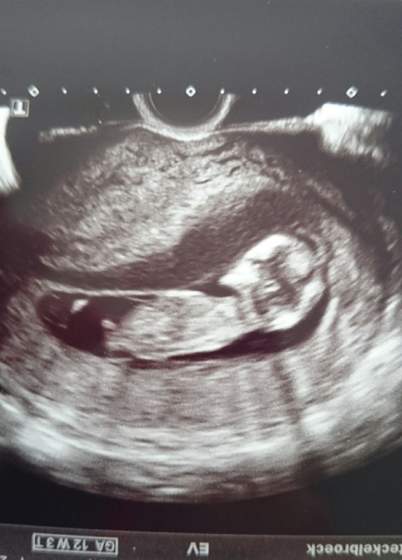

ma 7cm x1,5 cm (wcześniej miał 3,5cm nie wiem na ile, ale wiem na pewno ze to była wielka plama na szerokość) ale mam sie nim nie martwić, bo krwiak jest z dala od kosmówki czy tez łożyska (już nie pamietam) i nie zagraża wgl dziecku co było widać na usg, bo maluch spory już ma 6,9 cm serduszko wali jak dzwon